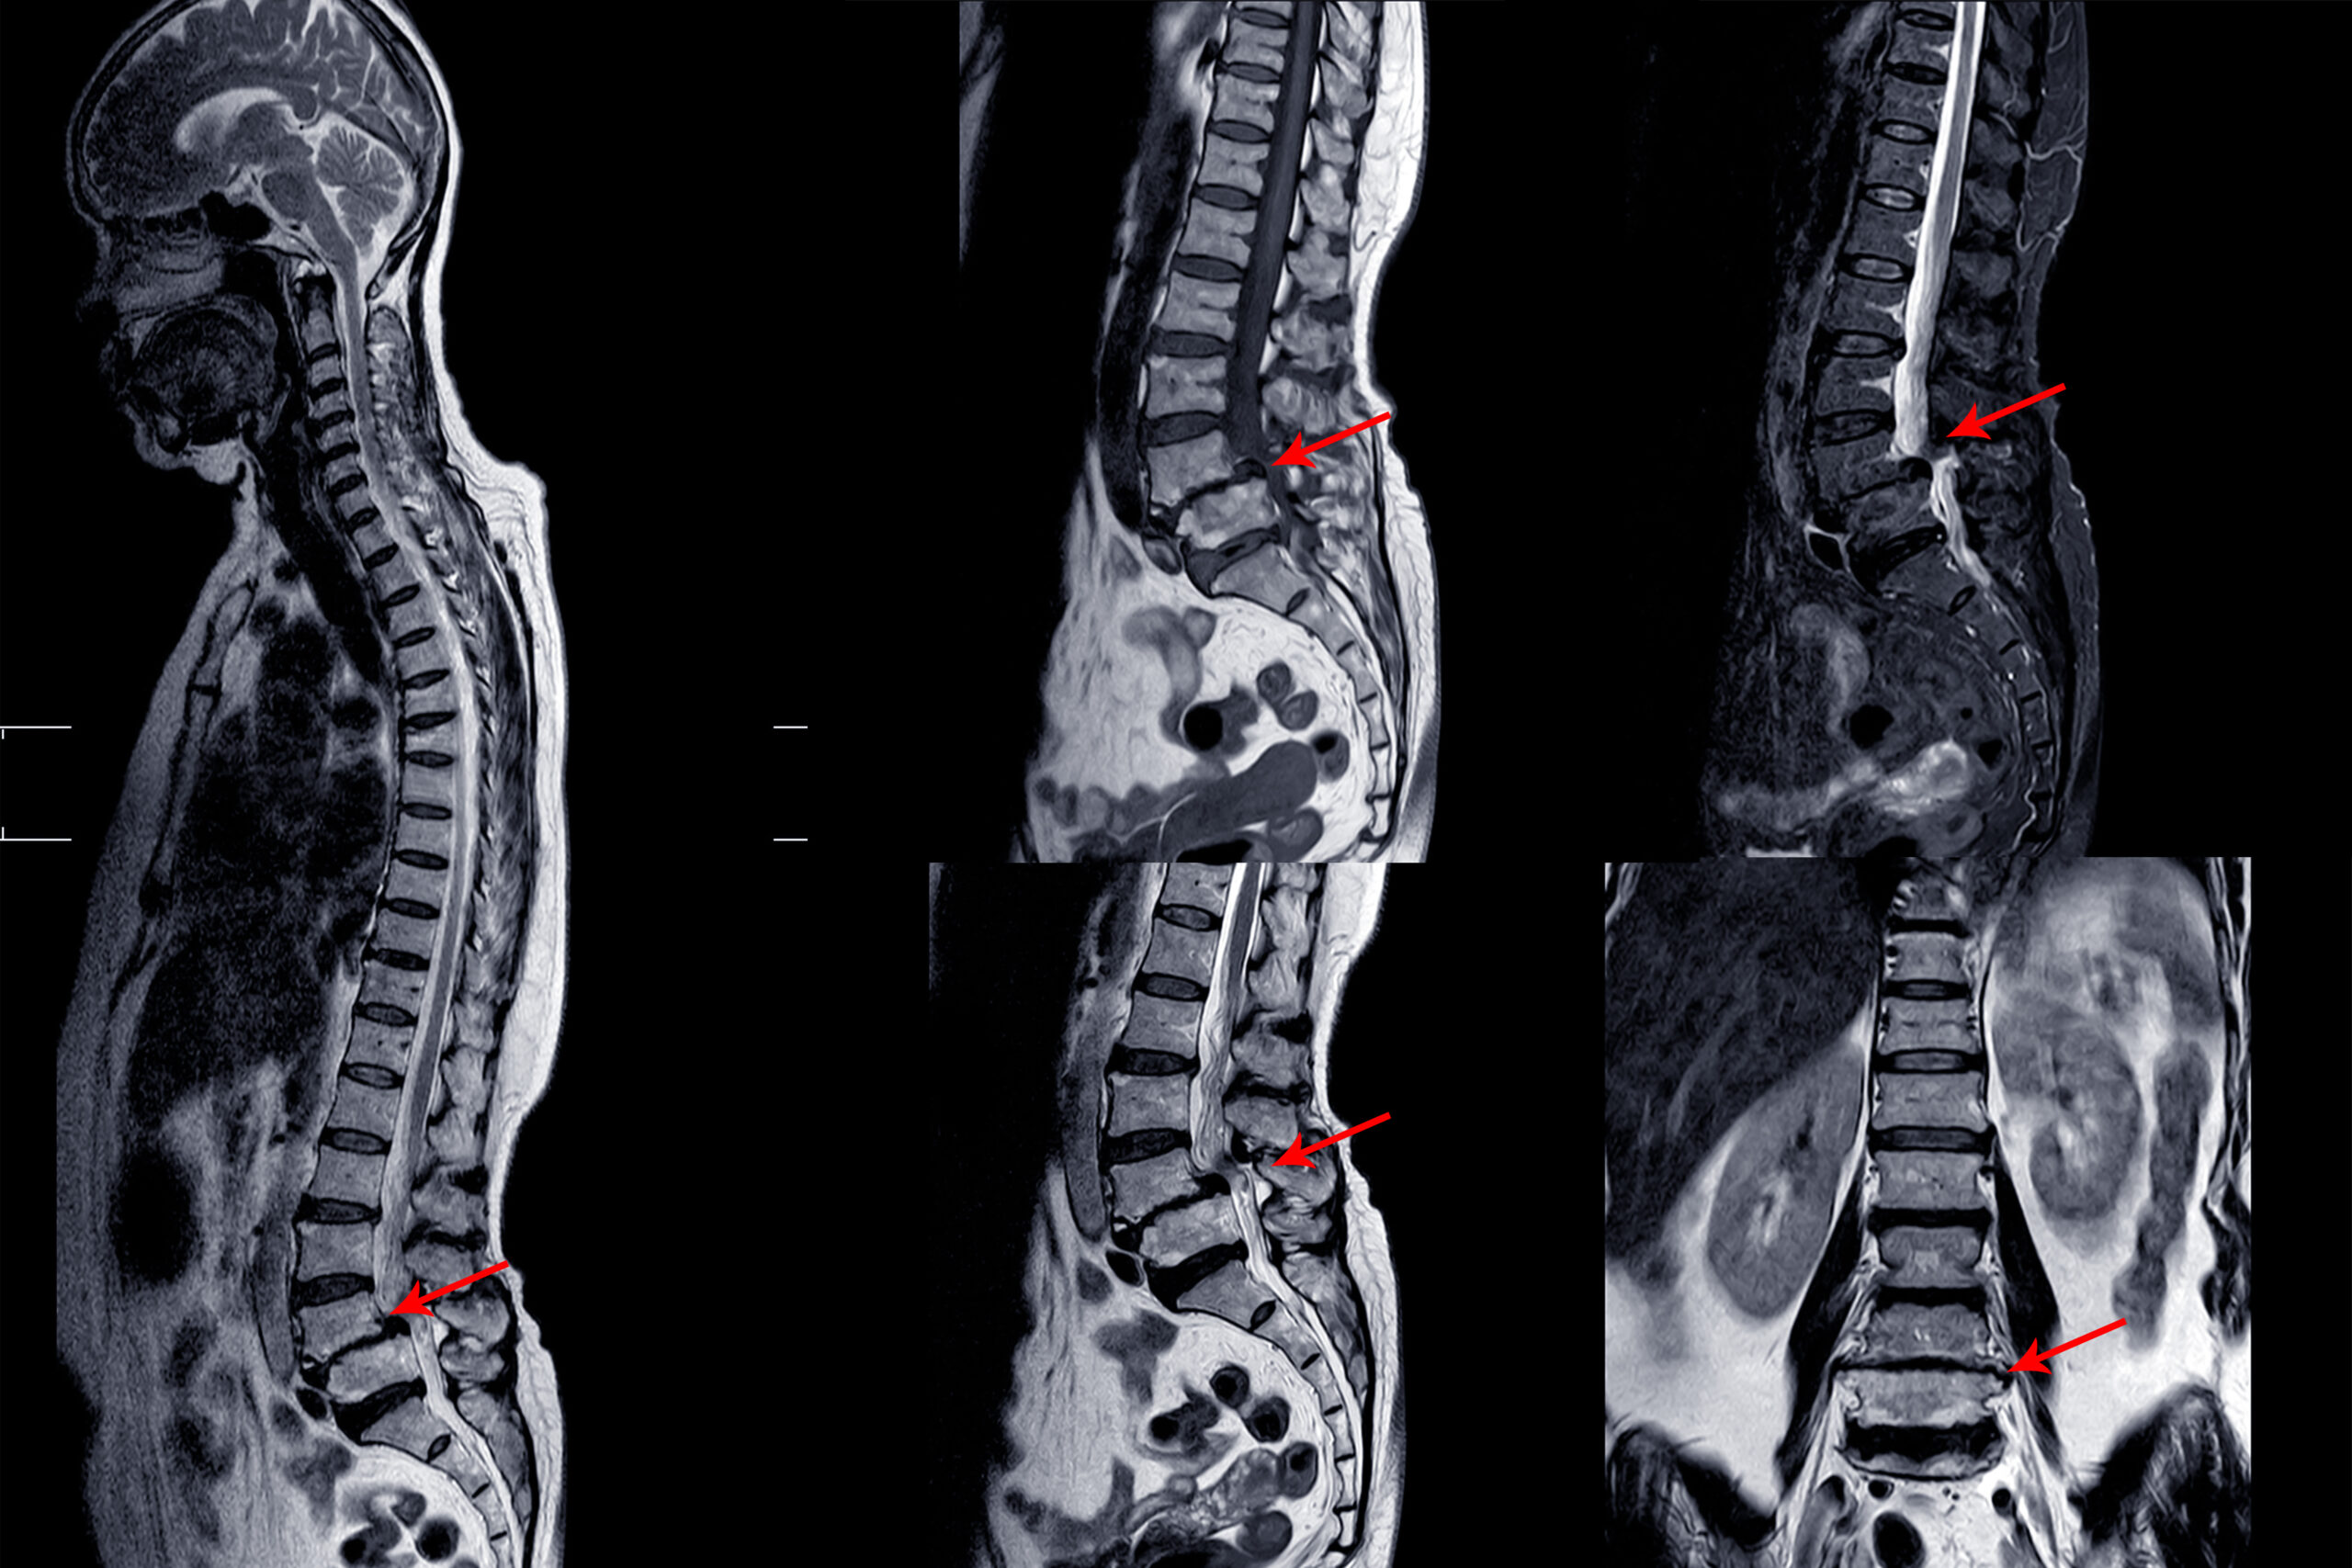

Lower back pain, radiating leg pain, or spinal instability caused by degenerative spine disorders can significantly affect a person’s mobility and lifestyle. As spinal surgeries continue to evolve, less invasive and more effective techniques are emerging. One such advanced method is Oblique Lumbar Interbody Fusion (OLIF) — a cutting-edge procedure that offers excellent spinal stability with reduced tissue damage and faster recovery.

OLIF (Oblique Lumbar Interbody Fusion) is a minimally invasive spinal fusion surgery that targets the lumbar (lower back) region. Unlike traditional posterior approaches that go through the back muscles, OLIF takes an oblique (angled) path through the abdomen’s side, avoiding major muscles and nerves. This approach minimizes trauma to soft tissues, reduces postoperative pain, and speeds up recovery.

• Lumbar spondylolisthesis (vertebral slippage)

• Disc collapse with nerve root compression

• Spinal stenosis